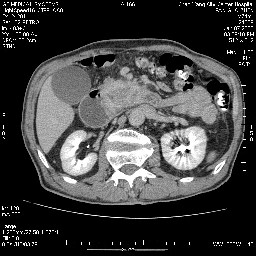

女,74岁,呕吐10余日

还有胃、脾之间可见有侧支循环建立。左肾盂积水。

双肾多发小囊肿;左肾积水。

十二指肠降段扩张,水平段狭窄成鼠尾状,肠壁明显增厚,胰腺勾突增大成不均匀强化,其内可见低密度区,胆囊增大,1十二指肠水平段腺癌侵犯胰腺勾突可能大,2胰腺癌侵犯十二指肠(只有胆囊增大没有肝内外胆管扩张不好解释)代除外.

支持壶腹mt侵及胰腺,那个椎体是骨疝吗???

十二指肠降段扩张,水平段狭窄成鼠尾状,肠壁明显增厚,胰腺勾突增大成不均匀强化,其内可见低密度区,胆囊增大,1十二指肠水平段腺癌侵犯胰腺勾突可能大,2胰腺癌侵犯十二指肠 。

今日手术结果:胰腺钩突癌侵犯十二直肠,腹腔淋巴结转移.